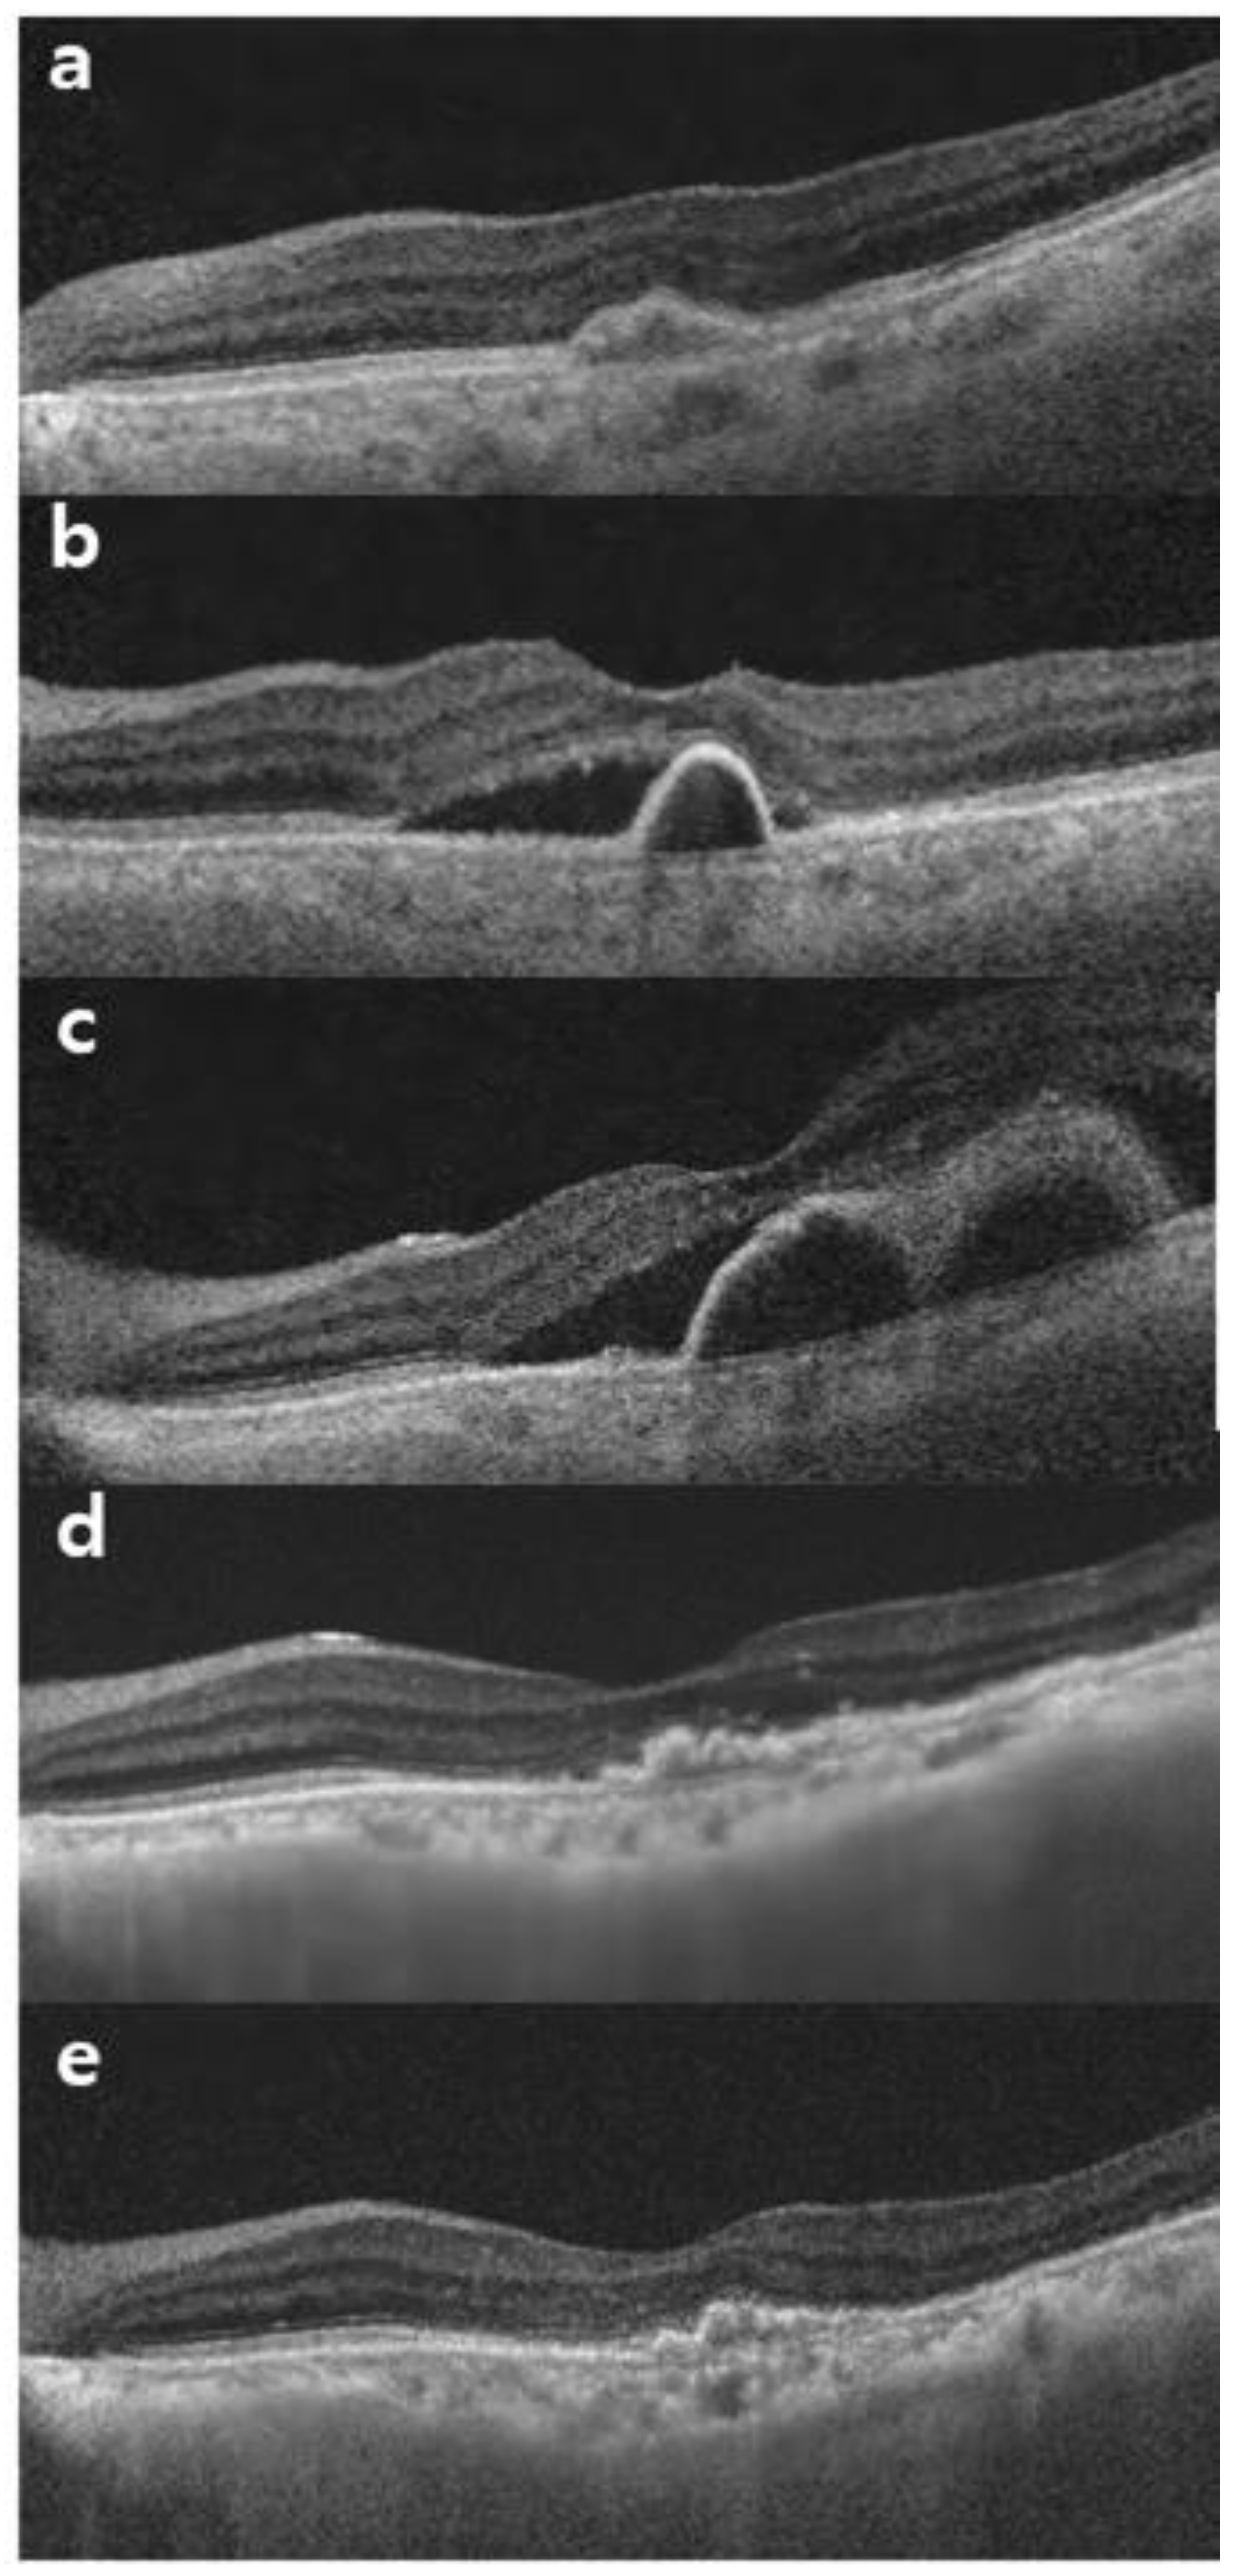

3.3.4. Intraocular Inflammation